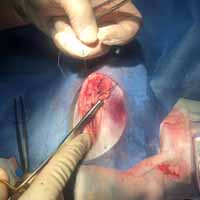

Bodrum Yalıkavak'taki kliniğimizde gerçekleştirdiğimiz yumuşak doku cerrahi uygulamaları:

Aslında bu cerrahi alan oldukça geniş bir alanı kapsamaktadır. Fakat siz yırtılan ya da kesilen deriye uygulanan cerrahi işlemler olarak düşünebilirsiniz. Daha detaylı anlatmak gerekirse; Örneğin; Erkek bir kedinin üriner taşlarından dolayı sondayla denenmesine rağmen açılmayan idrar kanalına yapılan dişileştirme operasyonu (perineal üretrostomi) da bir yumuşak doku cerrahisi operasyonudur.